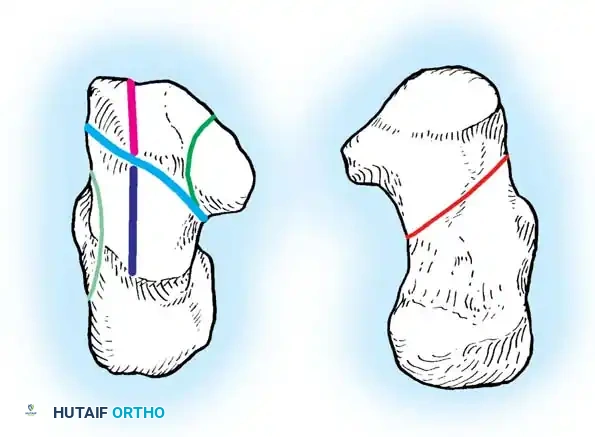

The Sanders Classification

The Sanders classification has become the universally accepted system for intraarticular calcaneal fractures. It is based on the number and location of articular fracture lines seen on the semicoronal CT image showing the widest portion of the posterior facet.

The posterior facet is divided into three potential fracture lines (A, B, and C), creating four potential fragments (lateral, central, medial, and sustentacular).

* Type I: All nondisplaced fractures (regardless of the number of fracture lines).

* Type II: Two-part fractures of the posterior facet (one fracture line). Subdivided into IIA, IIB, or IIC based on the location of the line.

* Type III: Three-part fractures (two fracture lines), featuring a centrally depressed fragment. Subdivided into IIIAB, IIIAC, or IIIBC.

* Type IV: Four-part (or more) highly comminuted fractures.

Clinical Pearl: Ebraheim et al. demonstrated that CT scans may occasionally underestimate the sagittal plane rotation of a depressed fragment. Therefore, plain lateral radiographs must always be correlated with CT findings to fully appreciate the three-dimensional deformity.